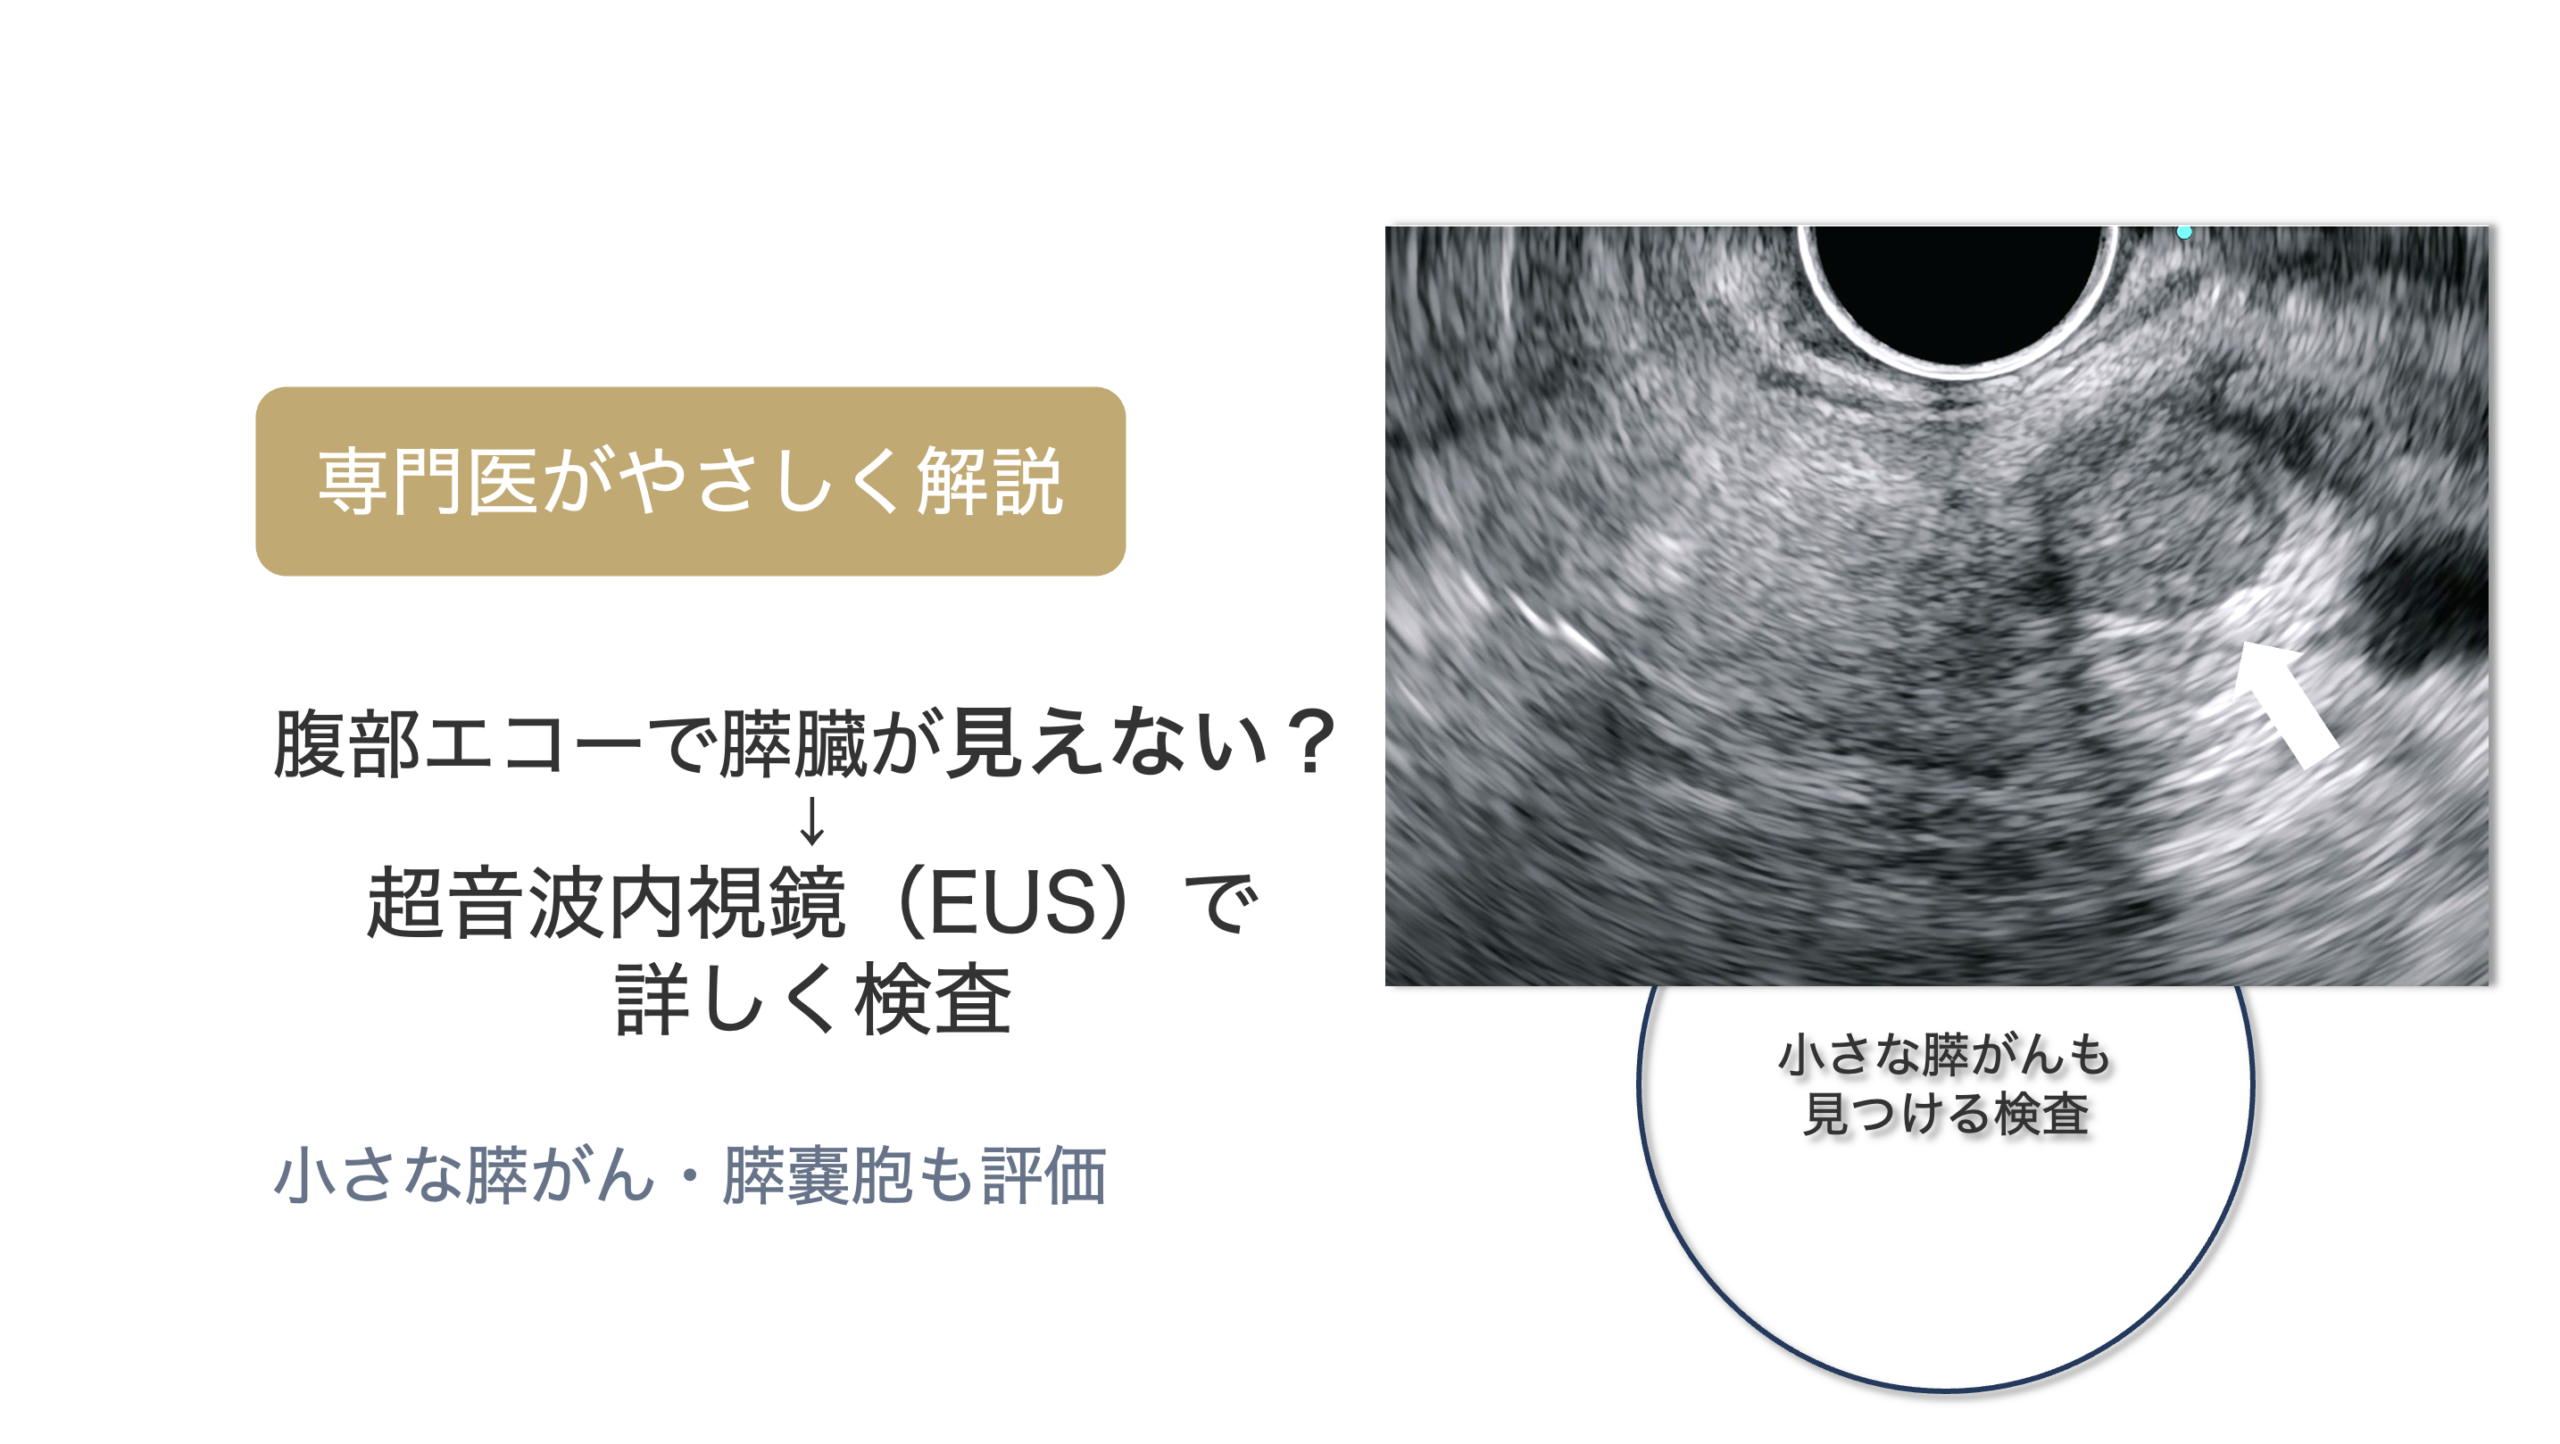

検査

バレット食道がんの診断には胃内視鏡(胃カメラ)が欠かせません。しかし、実はバレット食道がんの診断は、熟練した内視鏡医でも難しいことがあります。

<特殊光(NBI・TXI)での精密観察が重要>

そのため診断には、通常光に加えて、

NBI(狭帯域光観察)

TXI(構造・色調強調観察)

といった 画像強調内視鏡(IEE) を組み合わせて、粘膜の微細な血管・表面構造を詳細に観察します。

こうした特殊光観察は、数mmレベルの早期バレット食道がんの発見に非常に有用 です。